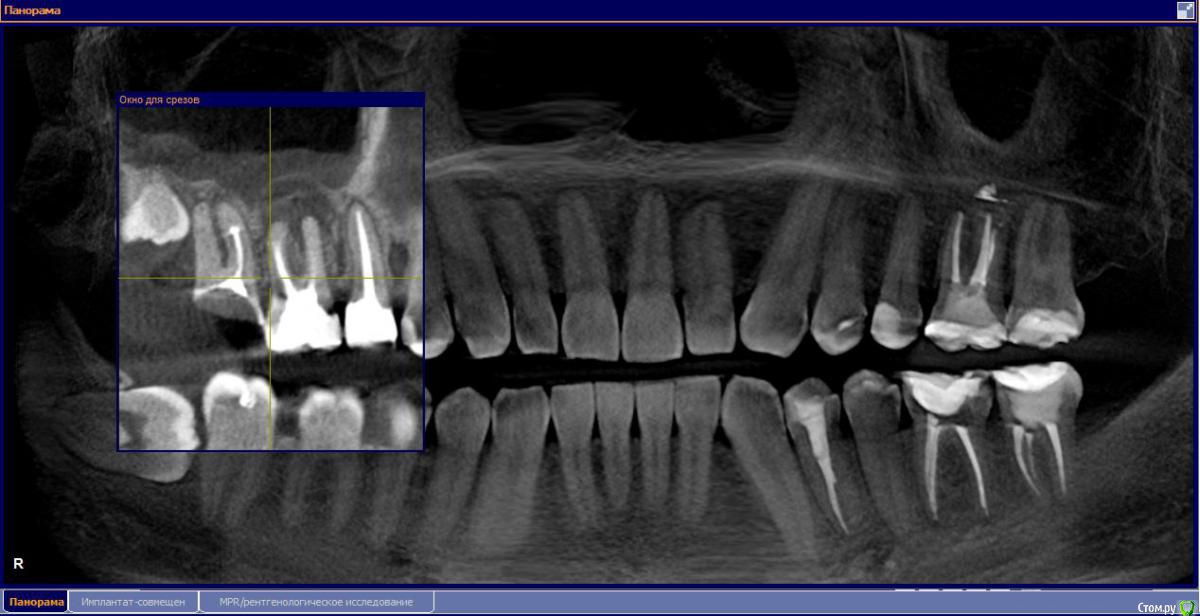

М, 33 года. Есть показания к одновременному удалению 16-го зуба - киста, и 17-го - разрушена верхушка. 8-й предлагают оставить, чтобы "держал кость" (как то так мне озвучили).

Через 3-4 месяца рекомендуют синус-лифтинг и установку двух имплантатов.

- Возможно ли консервативное перелечивание 16 зуба и есть ли смысл?

- Насколько опасная имеется киста?

снимки прилагаю.

и 6 и 7й зубы не выглядят 100% кандидатами на удаление.

1.6 большая вероятность сохранить,но понятнее при очном осмотре и диагностическом вскрытии. 1.7,скорее всего,не жилец,но тоже очно взглянуть на него стОит